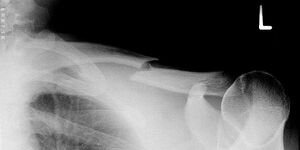

Gebrochenes Schlüsselbein - Erik Streb commons.wikimedia.org, CC BY-SA 3.0

Ein Schlüsselbeinbruch ist häufig die Folge von einem Sturz oder Schlag gegen das Schlüsselbein oder die Schulter, zum Beispiel beim Reiten, Fußball oder Skifahren. Dabei kann die bandartige Verbindung vom Schlüsselbein zum Schultergelenk reißen oder das Schlüsselbein brechen. Oft entsteht als Folge eine starke Schwellung und häufig ist eine Stufenbildung in der Schulter sichtbar.